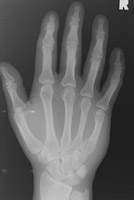

- Click on the image for a larger versionBPA radiograph of the hand. This details the appearance of an oblique fracture of the third metacarpal.